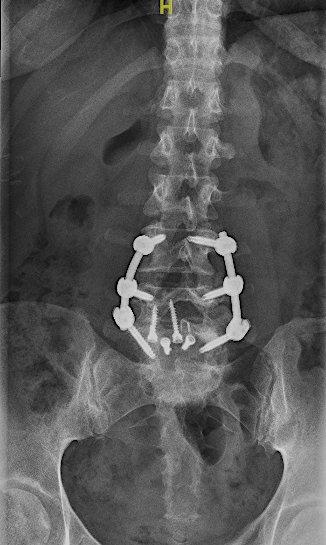

RX 6 meses